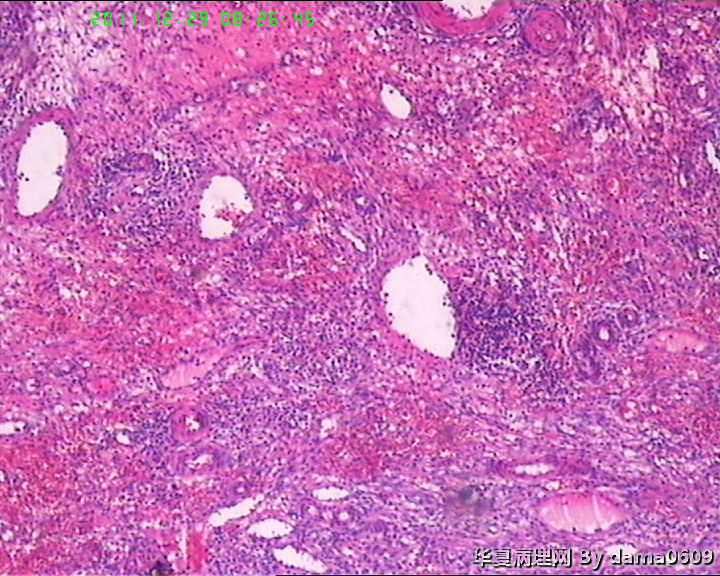

另一为小块囊壁样组织。镜下见卵巢间质内大量淋巴细胞、嗜酸性粒细胞浸润,间质出血。囊壁囊腔一侧见组织细胞、嗜中性粒细胞浸润,小血管增生(图1-9)。局灶见较多的平滑肌组织,内见有异位的子宫内膜组织(图10、11、12)。另于平滑肌组织间见到散在的小腺体(图13~30)。学生不解:1、老年人卵巢内可以出现平滑肌组织,如卵巢门处。此例如此多的平滑肌是正常的吗?   2、平滑肌间的小腺体若是异位的子宫内膜腺体但周围不见内膜间质成分。若非内膜异位腺体,学生又不知如何解释,尤其图19、20、21。请老师们指点迷津。感谢!!

• 感谢老师们一年来的支持,年终岁尾最后一贴,请老师们指教!!图10

图10

• 感谢老师们一年来的支持,年终岁尾最后一贴,请老师们指教!!图11

图11

• 感谢老师们一年来的支持,年终岁尾最后一贴,请老师们指教!!图12

图12